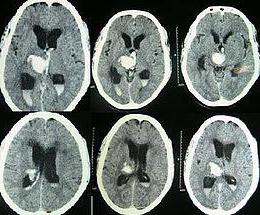

Увеличение ликвора и скопление его в межжелудочковых пространствах и под оболочками мозга ведет к повышению внутричерепного давления. Называется такое состояние гипертензионно-гидроцефальный синдром. Признаки его хорошо видны при проведении специального обследования — компьютерной томографии: расширение полостей с ликвором и сдавливание, уменьшение мозгового вещества. Именно такие процессы служат основой клинической картины ГГС — головные боли, тошнота, нарушения зрения, внимания, способности к обработке полученной информации, апатии и раздражительности.